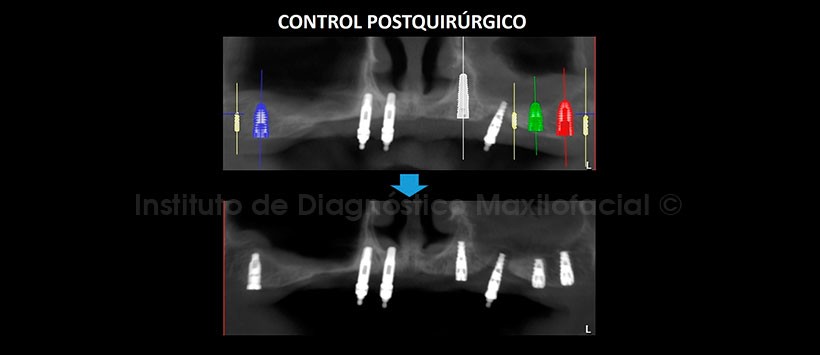

En la tomografía de control post quirúrgico (Figura 7, 8, 9, 10 y 11), se aprecia los implantes con estructura ósea circundante, en las posiciones donde fueron planificadas virtualmente.